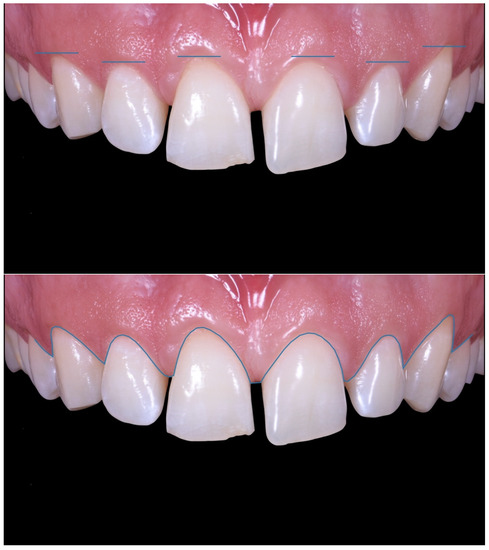

Case Report